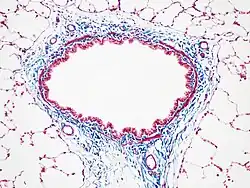

- Trichrome de Masson[2],[3]: coloration histologique associant à l'hématoxyline (coloration nucléaire), la fuchsine-Ponceau (coloration cytoplasmique) et le vert lumière ou le bleu d'aniline (coloration élective du collagène).